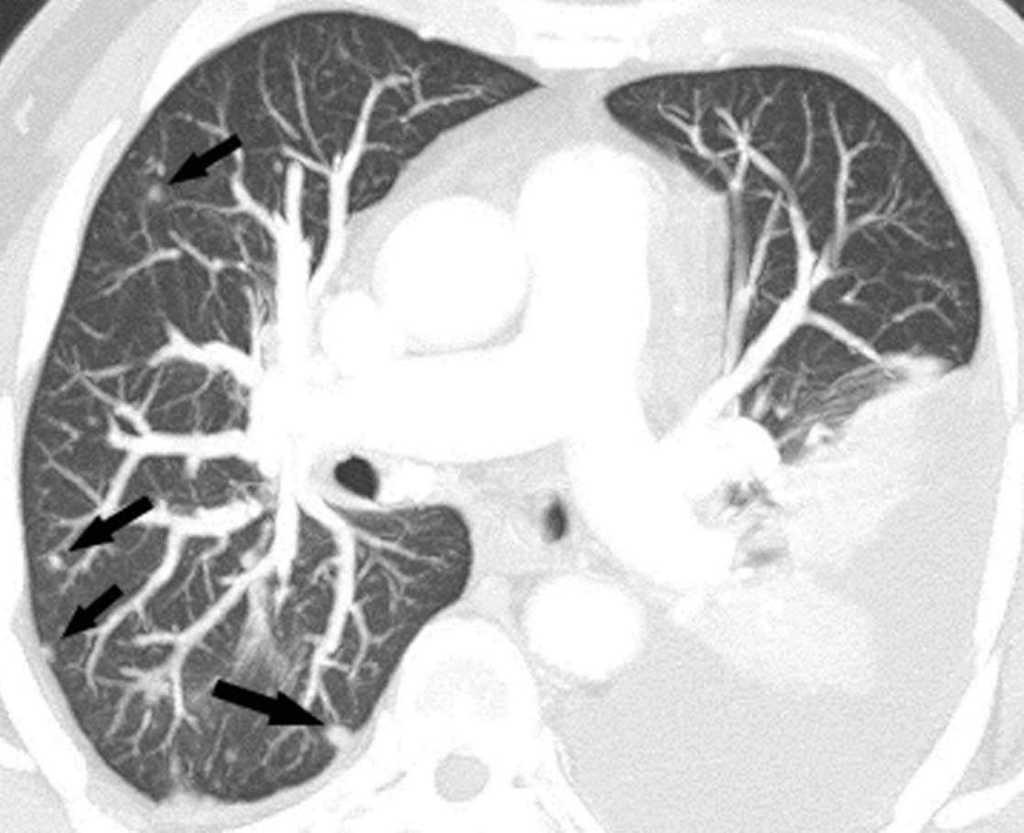

Pese a las conocidas limitaciones de la TC, ésta continúa siendo la técnica de elección en la estadificación del tumor en los pacientes con CPNM; su sensibilidad y especificidad en la determinación de la infiltración de pared oscilan entre el 38 y el 87% y del 40 al 90%, respectivamente, según las series. El desarrollo de nuevos equipos de TC helicoidal y principalmente las TC multidetectoras (TCMD) proporcionan unas imágenes 2D de mayor resolución con la posibilidad de hacer reconstrucciones multiplanares (MPR) en distintos planos del espacio e incluso 3D con la consiguiente mejora de la valoración del tumor, su extensión e infiltración de estructuras vecinas5 (fig. 4). Así, con la TCMD se puede poner de manifiesto con mayor fiabilidad la invasión de la cisura, la pared torácica o el mediastino, y además es capaz de determinar, gracias a las reconstrucciones de volumen, la relación exacta del tumor con la vía aérea (fig. 5). El progreso en la capacidad diagnóstica deriva del incremento en la resolución de las imágenes obtenidas y de la posibilidad de emplear nuevas aplicaciones como la broncoscopia virtual y la visualización en tiempo real. La broncoscopia virtual es útil para valorar la invasión del árbol traqueobronquial con la finalidad de planificar la cirugía, también como guía para el fibrobroncoscopista y, por último, porque permite ver el árbol bronquial distal a la estenosis (fig. 6)6. La capacidad de ver la imagen en tiempo real es especialmente útil cuando se emplea como guía en maniobras intervencionistas como biopsias percutáneas, ya sea con finalidad diagnóstica o como parte de la estadificación (fig. 7). Esta técnica de guía de biopsia denominada TC fluoroscopia reduce el número de pases y el tiempo global de la exploración, implica un menor riesgo de lesión de estructuras y permite la visualización inmediata de las posibles complicaciones7.

Fig. 5.--Invasión vía aérea. Tomografía computarizada (TC) torácica con contraste. Corte axial (A) que muestra masa hiliar izquierda con afilamiento del bronquio lobar superior (flecha blanca) y adenopatía subcarinal (flecha negra). (B) Reconstrucción de volumen con amputación del bronquio (flecha negra).